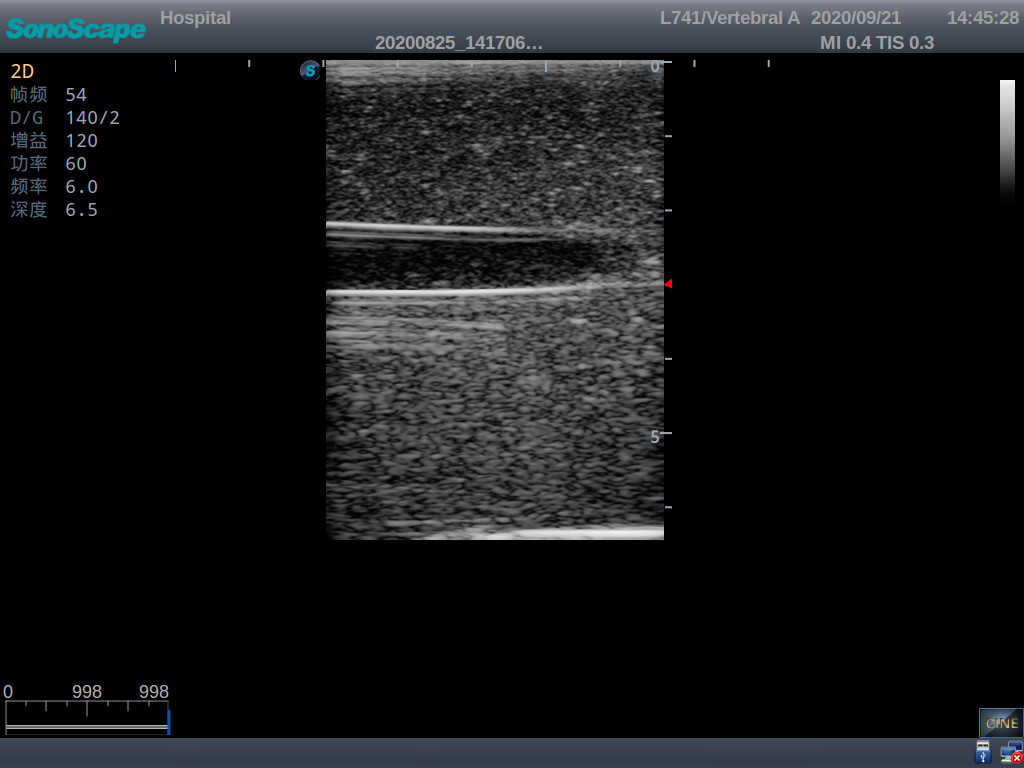

1) Made of high molecular polymer ultrasound material, close to real skin. It can conduct ultrasound-guided puncture exercises with various clinical models of real ultrasound machines

2) Clear and real images of arteries and veins